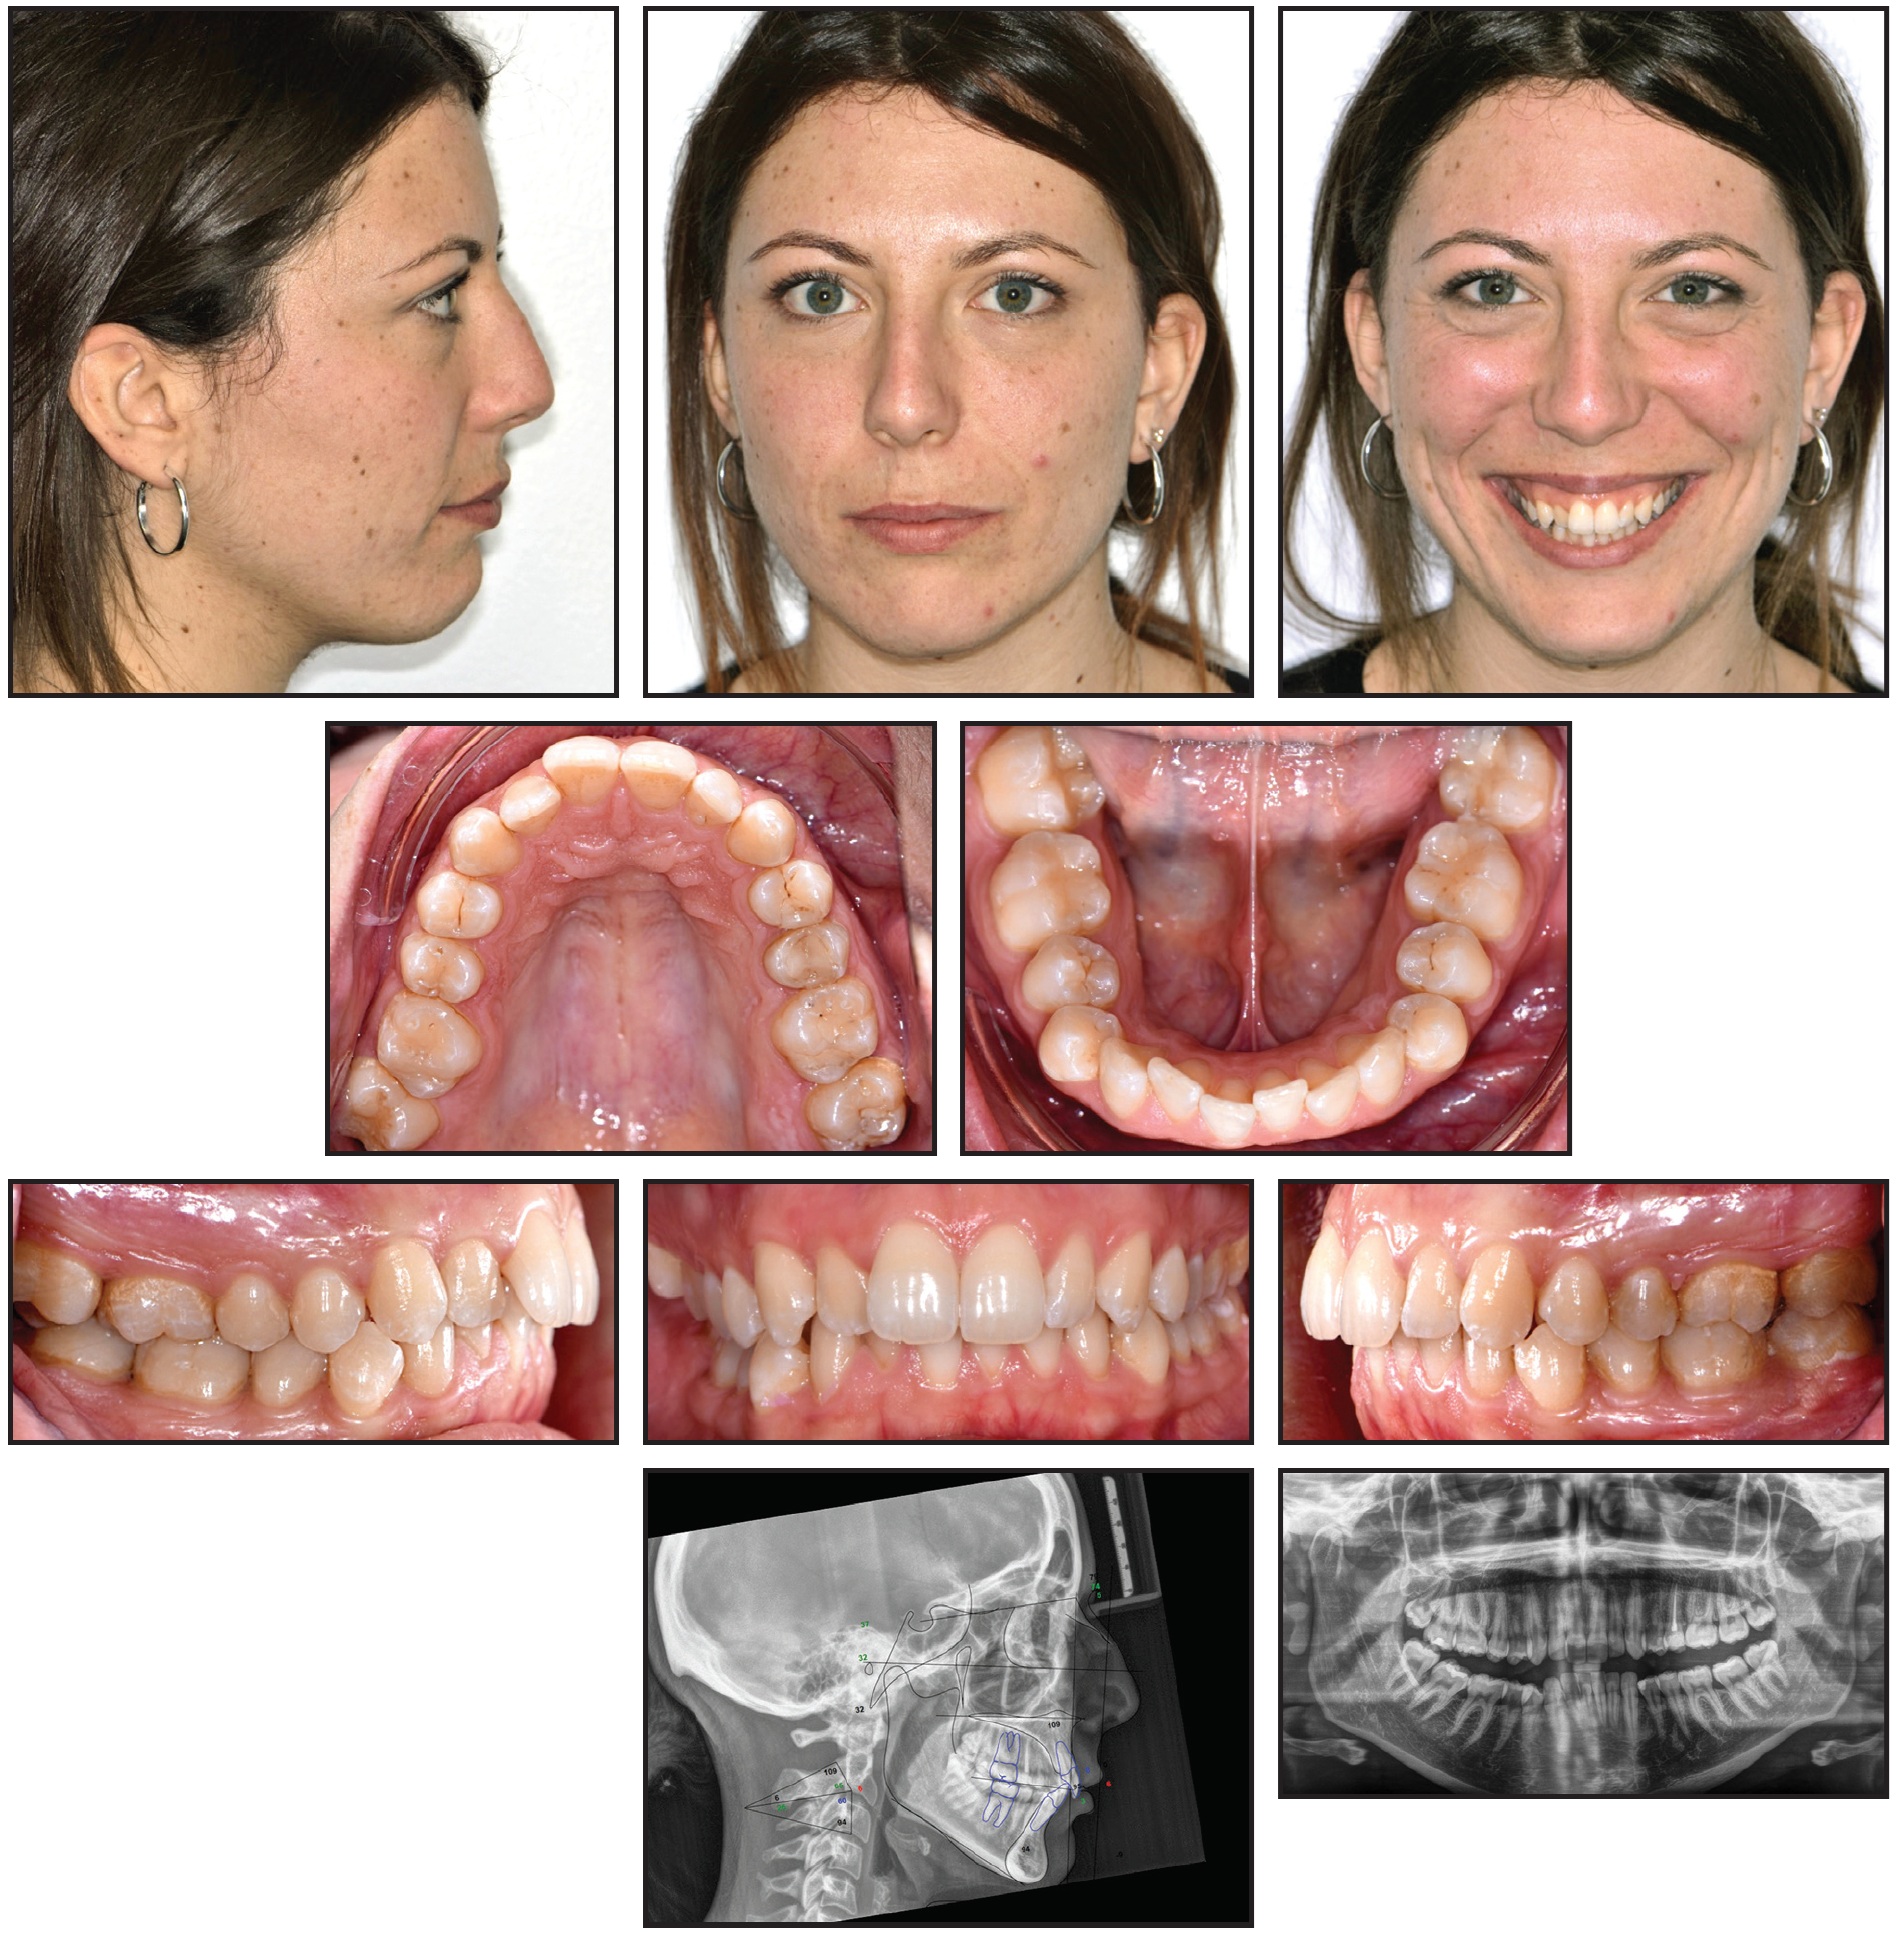

A 27-year-old female presented with the chief complaint of unsightly front teeth and traumatic biting in the right posterior cheek region (Fig. 1A).

Fig. 1 27-year-old female patient with borderline Class I molar and canine relationships, moderate crowding in both arches, and scissor bite involving upper and lower right second molars before treatment (continued in next image).

Extraoral analysis found a convex profile, a long lower third of the face, and lip strain from the attempt to achieve lip competence. The patient had a gummy smile with complete incisor exposure, bilateral buccal black corridors, and a slight occlusal cant. She had borderline Class I molar and canine relationships with excessive overbite and overjet. The lower midline was deviated 1mm to the left of the upper midline, and the curve of Spee was accentuated on both sides. Moderate crowding and malalignment were present in both arches. A scissor bite of the upper and lower second molars was observed on the right side (Fig 1B).

Fig. 1 (cont.) 27-year-old female patient with borderline Class I molar and canine relationships, moderate crowding in both arches, and scissor bite involving upper and lower right second molars before treatment.

The patient did not report any TMJ symptomatology, as confirmed by the clinical and functional exam. All teeth were present on the panoramic radiograph. Cephalometric analysis (Table 1) indicated a moderate biretrusive skeletal Class II (ANB = 5.5°) with a primarily mandibular component (SNB = 73.8°) and a hyperdivergent pattern (FMA = 31.5°). Upper and lower incisor inclinations seemed to be normal.